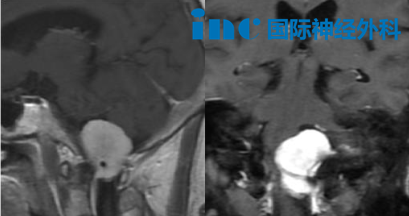

39岁的武女士,颅咽管瘤术后第1天,和巴教授热情交流,最新影像核磁显示非常好,垂体柄保留完好。

武女士的鞍区颅咽管瘤虽然体积不大,但位置深在,且毗邻视神经和下丘脑等关键结构,手术难度并不低。术者的目标不仅是尽可能切除肿瘤,更重要的是保留垂体柄及其周围重要组织——这直接关系到武女士术后的生活质量。2026年4月20日,巴教授作为北京天坛医院神经外科外籍专家,成功为她实施了开颅手术。

术后第1天,巴教授前来查房,武女士一看到他就露出开心的笑容。巴教授问她:"今天感觉怎么样?"她毫不犹豫地回答:"非常好,特别好!"当巴教授用手机记录她的恢复情况时,她还开心地对着镜头比了个"yeah"。巴教授随后告知了她术后核磁检查的结果:"我看过了今天的核磁,非常好。垂体柄看得很清楚,保留完好。"